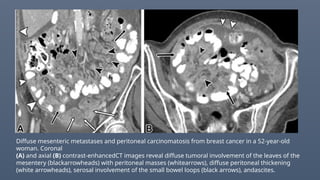

Diffuse mesenteric metastases and peritoneal carcinomatosis from breast cancer in a 52-year-old

woman. Coronal

(A) and axial (B) contrast-enhancedCT images reveal diffuse tumoral involvement of the leaves of the

mesentery (blackarrowheads) with peritoneal masses (whitearrows), diffuse peritoneal thickening

(white arrowheads), serosal involvement of the small bowel loops (black arrows), andascites.